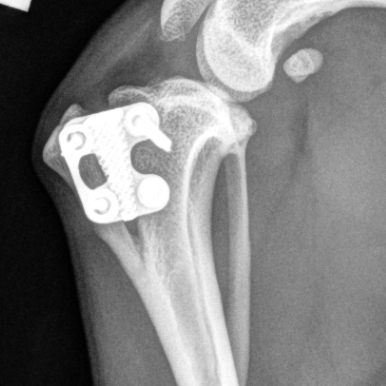

- TTA RAPID Technique: Learn the principles and steps involved in the TTA RAPID® technique, a minimally invasive approach to addressing CCL ruptures. This includes planning the surgery, making precise bone cuts, and utilizing pre-assembled implants for stabilization.

- RAPID Luxation Technique: The course covers the RAPID Luxation Technique, focusing on the addition of a patella luxation spacer to the TTA RAPID Cage. This addresses cases where both CCL injury and patella luxation are present, offering a comprehensive treatment solution.